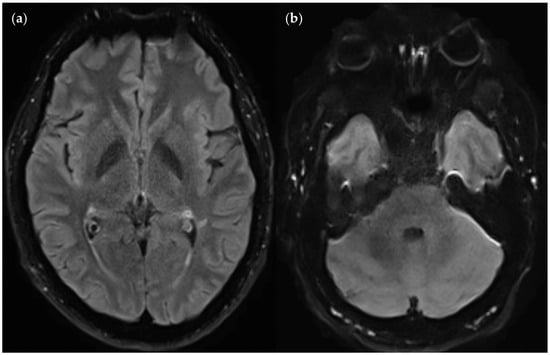

3.3.3. Positional Dependence of SNR and CNR in FLAIRUF

4.3. Limitations of the FLAIRUF Images

4.5. Outcomes Correlated with Technical Features